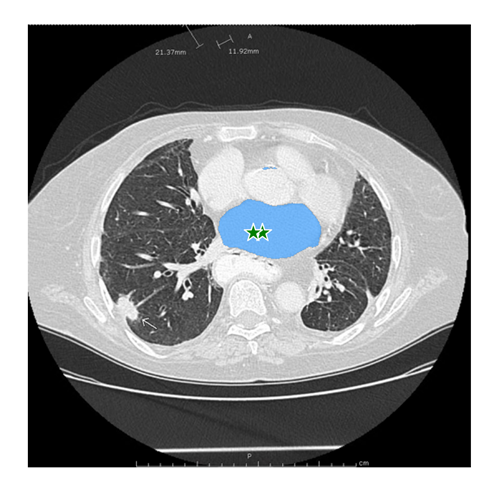

单个提示点通常会存在歧义的影响,因为可能多个目标均包含该点。为了得到我们想要的单个目标,我们可以在目标上进行多个点的提示,以获取该目标的分割结果。如果我们想要剔除,可以使用背景点(label=0),将其他部分剔除掉。

input_point = np.array([[270, 240], [260, 240]])

input_label = np.array([1, 1])

mask_input = logits[np.argmax(scores), :, :] # Choose the model's best mask

masks, _, _ = predictor.predict(

multimask_output=False,